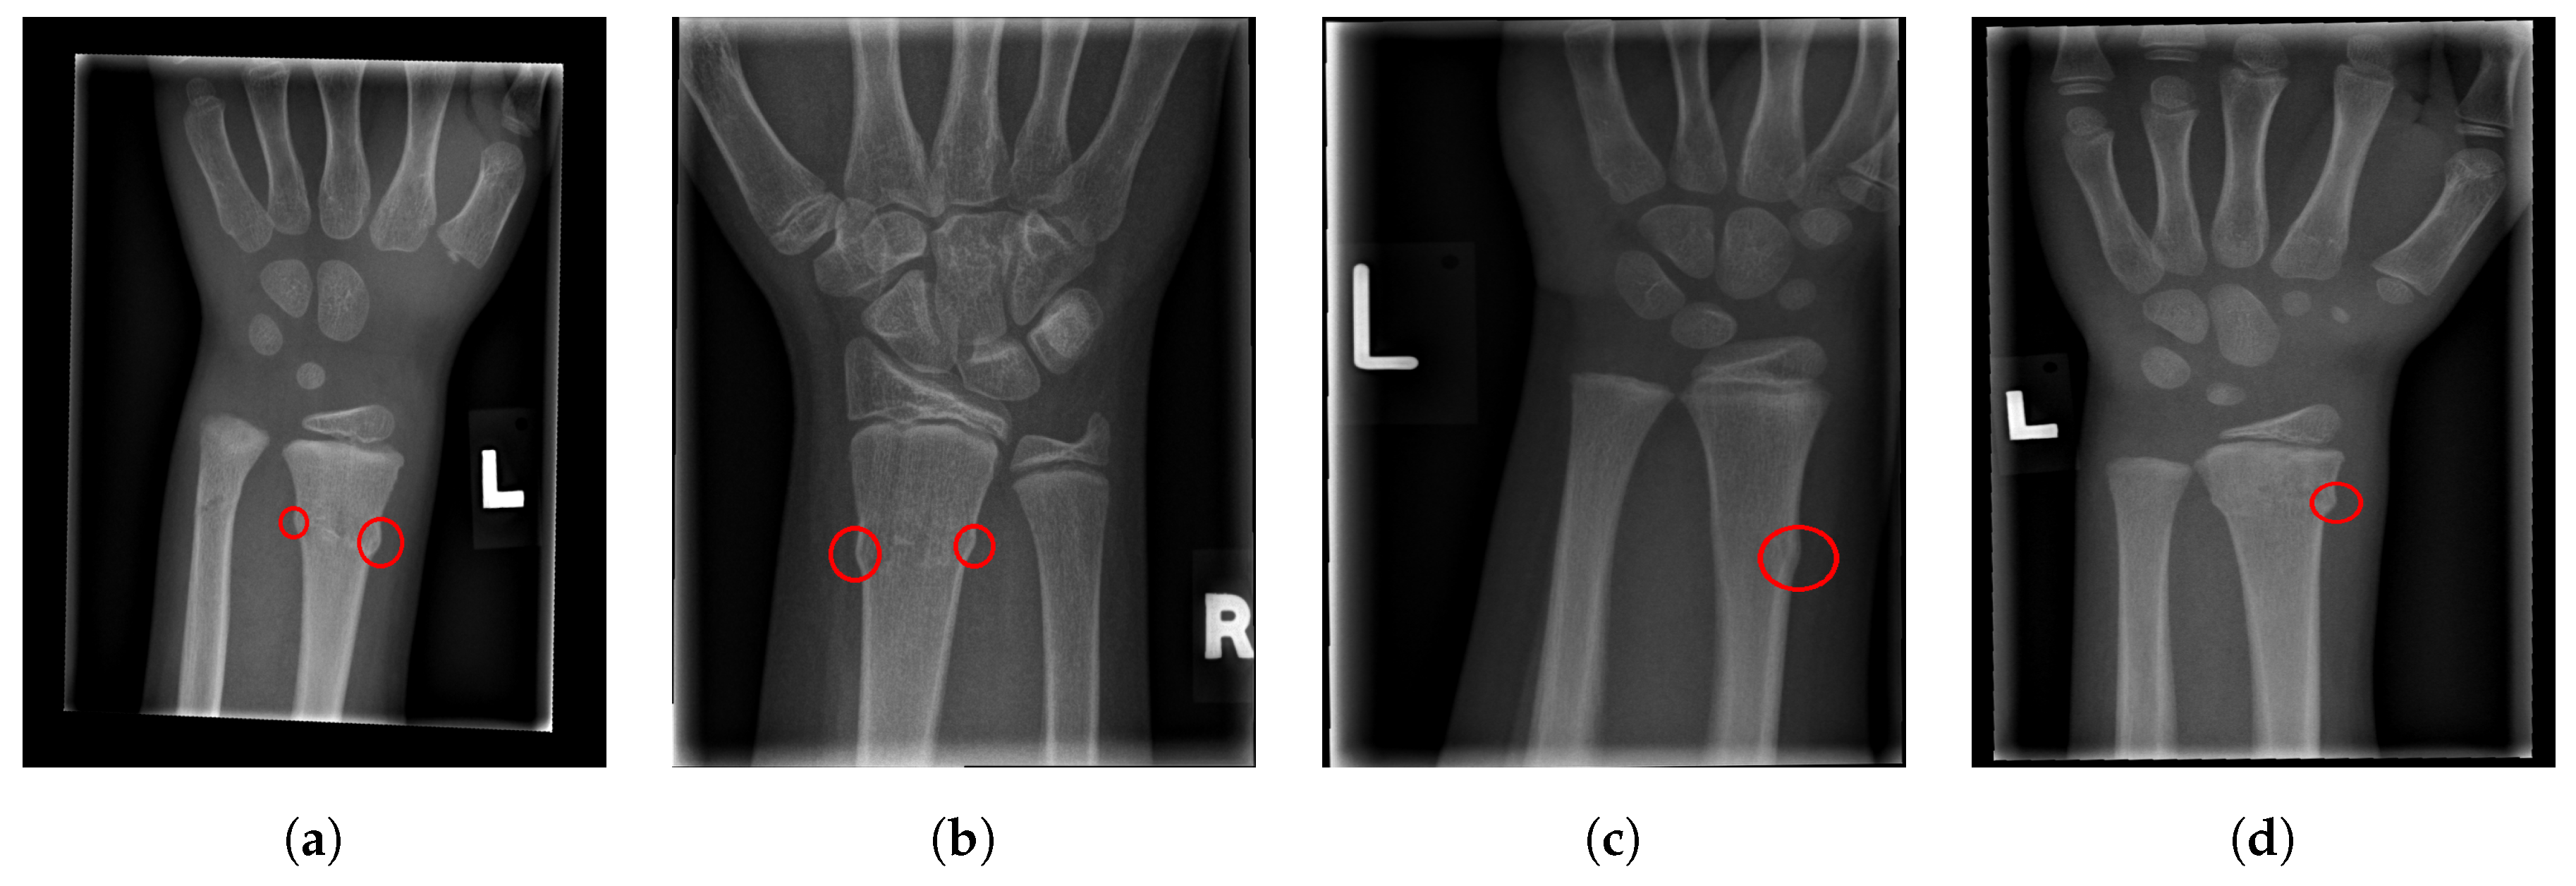

2.5. Fracture Detection

- True Positive (TP): The case when the image contains a fracture and the algorithm marked it as fractured, and at least one of the present fractures is correctly marked.

- False Negative (FN): The case when the image contains a fracture, but the algorithm failed to mark the image as fractured.

- True Negative (TN): The case when the image does not contain a fracture and the algorithm did not mark it as fractured.

- False Positive (FP): The case when the image does not contain a fracture, but the algorithm marked it as fractured and marked a fracture that is not present.